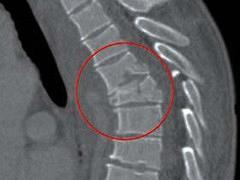

Rugpijn is een veelvoorkomend probleem in onze maatschappij. Bij deze patiƫntengroep is het van belang om als eerste stap specifieke rugklachten (klachten met een definieerbare oorzaak) te onderscheiden van aspecifieke rugklachten (klachten zonder definieerbare oorzaak). De rode vlaggen bieden hiervoor aanknopingspunten en bij de aanwezigheid van rode vlaggen dient een verwijzing plaats te vinden naar de tweede lijn. Het is van belang dat alle disciplines dezelfde alarmsignalen gebruiken en het belang daarvan inzien. Om een brug te slaan tussen eerste en tweede lijn geeft dit artikel geeft een overzicht van de pathofysiologie, diagnostiek en het klinisch beeld van de meest voorkomende wervelkolomaandoeningen.